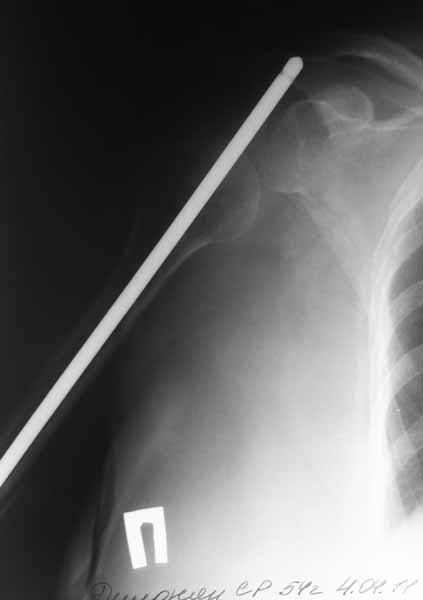

Спустя 6 месяцев после операции пациентка госпитализирована к нам в клинику. После выполнения контрольных рентгенограмм помимо атрофичного ложного сустава н\3 плечевой кости был диагностирован нижний вывих головки плечевой кости.

Первым этапом выполнено удаление металлоконструкции и БИОС плечевой кости с костной аутопластикой плечевой кости. Послеоперационный период без особенностей. Пациентка получила полный курс электромиостимуляции.